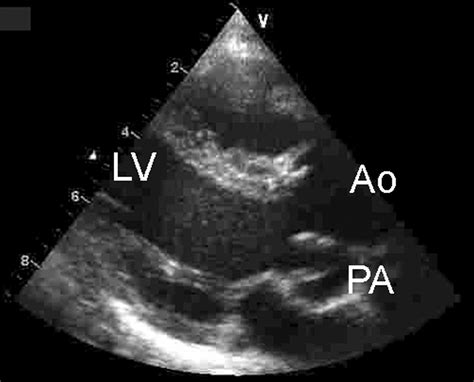

Echocardiography is a non-invasive imaging technique that uses ultrasound waves to visualize the heart's structure and function. It is the primary diagnostic tool for evaluating the Left Ventricle Outlet. Echocardiography can assess the aortic valve's structure and function, visualize any obstructions in the Left Ventricle Outlet, and measure the pressure gradient across the outlet. It can also evaluate the left ventricle's size, shape, and function, providing a comprehensive assessment of cardiac health.

There are several types of echocardiography, including transthoracic echocardiography (TTE), transesophageal echocardiography (TEE), and stress echocardiography. TTE is the most commonly used technique, providing a non-invasive and cost-effective way to evaluate the heart. TEE, on the other hand, involves inserting a probe into the esophagus and provides higher-resolution images of the heart's structures. Stress echocardiography involves performing echocardiography during exercise or pharmacological stress to assess the heart's response to increased demand.